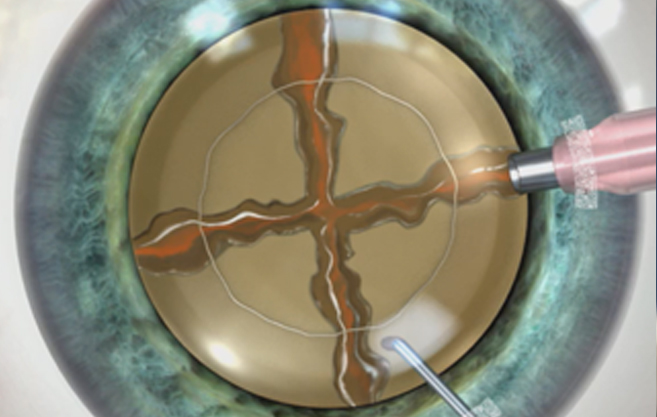

절개 부위가 고정된

레이저 다면 절개

vs

수정체낭 절개